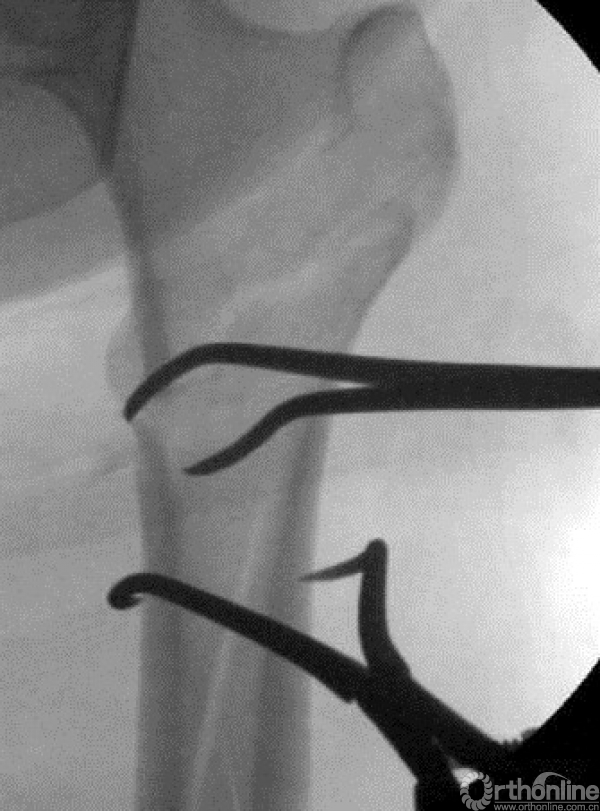

对于多端的骨折,需要善于应用阻挡钉技术。

摇杆技术+金手指技术进行复位。

远端时,防止后倒和摆动增加阻挡钉。